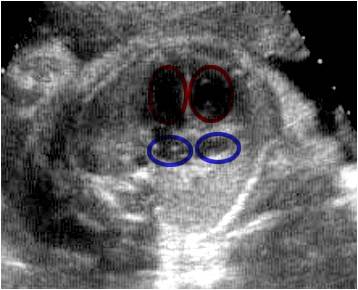

Septación normal del corazón

Ecografía fetal que muestra la septación normal del corazón, con sus cuatro cámaras: dos ventrículos (círculos rojos) y dos atrios (círculos azules). Compárelo con la aplicación 1.